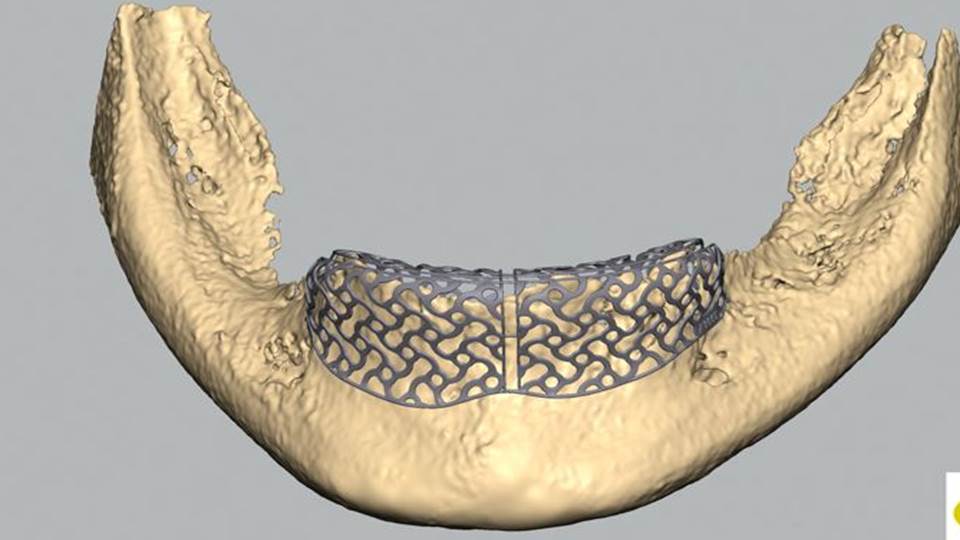

Alternativ setzen wir auch sogenannte Membranen ein, mit denen die Kieferkontur nachempfunden wird. Mit Hilfe von Titanverstärkungen können wir diesen eine Form geben, in die das Knochenwachstum sich hineinbewegt. Der Vorteil in der Verwendung von Membranen liegt darin, dass die Implantate in den meisten Fällen gleichzeitig gesetzt werden können.

Ein weiteres sehr innovatives Verfahren, das wir bei extrem großen Defekten einsetzen, ist das Reoss-System. Dabei wird basierend auf einem 3D-Röntgendatensatz die natürliche Form des Kiefers rekonstruiert und ein individuelles Gerüst für den Kieferaufbau modelliert. Wir setzen diese Verfahren nur mit Eigenknochen ein, den wir je nach Situation im günstigsten Fall gleich bei der Implantatbohrung gewinnen.